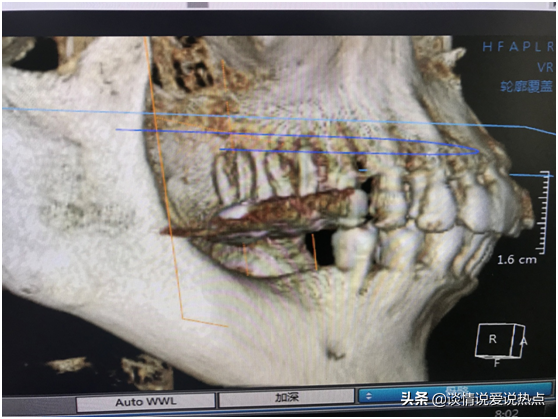

下圖是我現(xiàn)在右邊的牙齒,上頜做了根管調(diào)節(jié)戴冠,下頜缺失要種兩顆。醫(yī)生說我經(jīng)常用上頜咬東西,上頜有一顆戴冠的已經(jīng)伸長了,如果我再不管,三顆都會伸長。